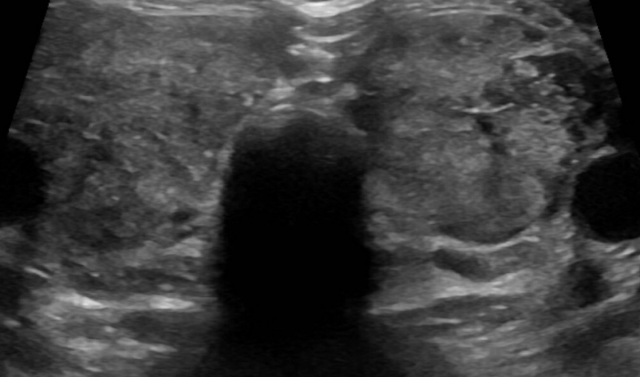

Medullary thyroid cancer (MTC) is a rare form of cancer that accounts for less than 2% of all thyroid cancers ...